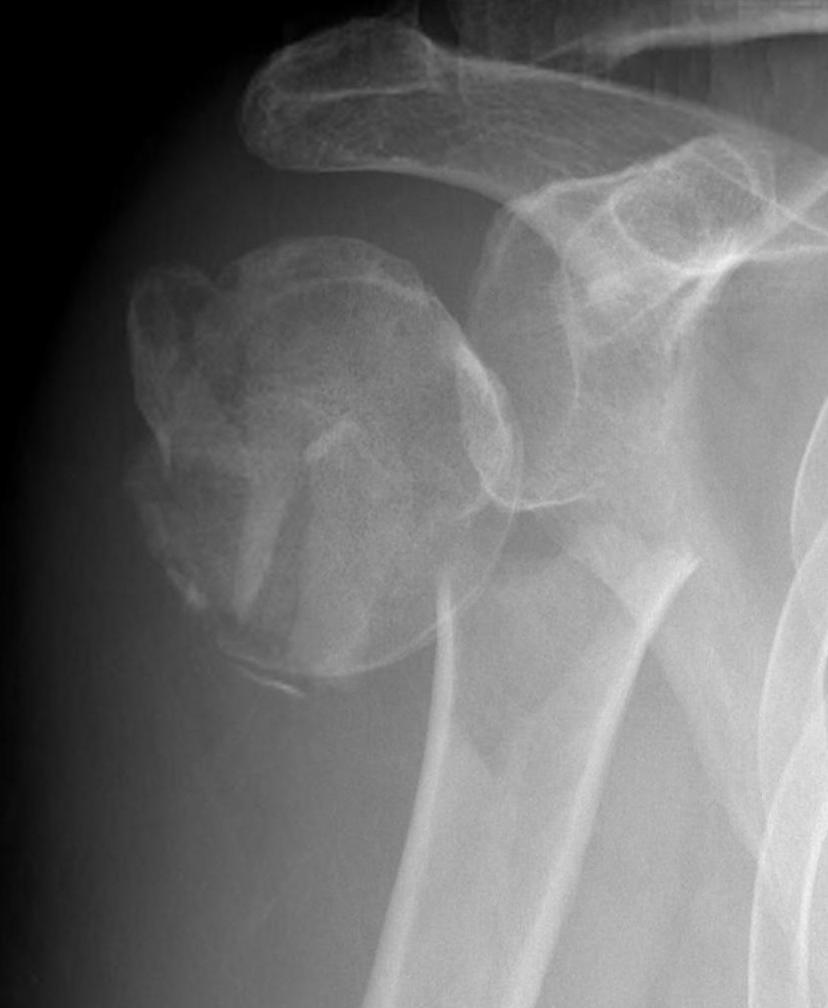

Four part

Avascular necrosis (AVN)

In most fractures, arcuate artery is disrupted, but head survives

- posterior circumflex artery is sufficient

- risk increases with amount of displacement

- 4 part fracture 30%

- 3 part fracture 15%